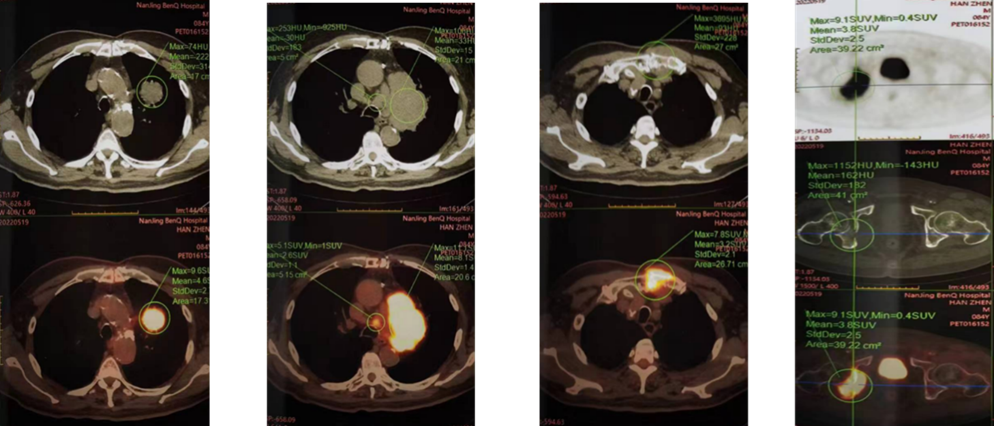

▌影像学检查

2022-05-19 PET-CT:左肺上叶纵隔见3.8cm×3.5cm类圆形分叶状肿块,主动脉弓旁及左肺门见多发大小不等淋巴结,部分有融合,较大横断面约8.8cm×5.8cm大小,FDG代谢均异常增高;胸骨切迹上方、纵隔内气管前、主肺动脉窗、隆突下另见多发短径小于1.9cm淋巴结,FDG代谢不同程度增高,胸骨上段左侧部分、右侧耻骨、坐骨髋臼部位见溶骨性骨质破坏伴软组织肿块形成,FDG代谢异常增高;右侧股骨上段髓腔内见小结节状FDG代谢增高影。